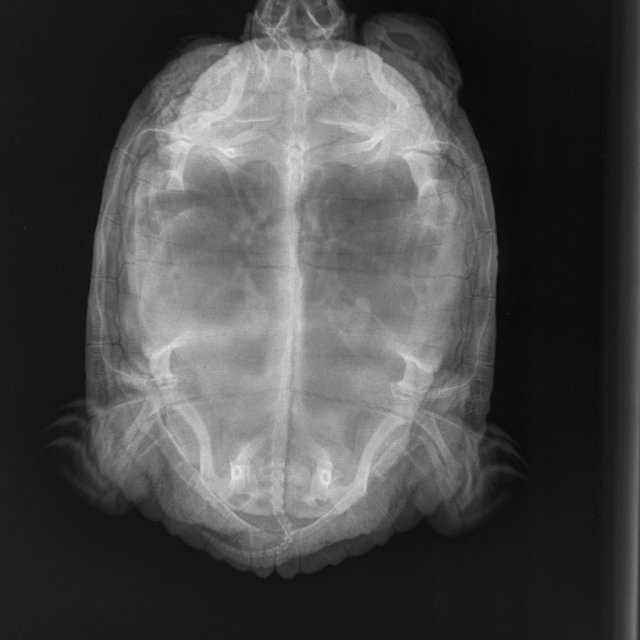

Я из Москвы, мне 49 лет. Черепаха красноухая, 10 лет, вес 1 кг 700 гр. живёт в аквариуме большом, есть лампа УФ и накаливания (включены целый день, меняем раз в полгода), есть фильтр внешний, нагреватель, мостик, грунта нет. Очень вялая - целый день отдыхает или спит, есть особо не хочет - рептомин не ест, грудку или печень раз в 5 дней после уговоров может съесть порцию небольшую, меньше чем её голова. Заметили болезнь уже недели три назад, две недели делали уколы. Последний укол 16 апреля. Прокололи курс лекарств по совету герпетолога - Кальций борглюконат через день,  Витам (1 раз в 3 суток), дексаметазон, фуросемид. По старому рентгену герпетолог сказал, что возможно яйца жировые, по свежему рентгену он никаких яиц не видит. Сейчас ничего больше не назначили нам. Я очень за черепаху волнуюсь

Рентген 2 нед назад (2).JPEG

Рентген 2 нед назад.JPEG

Рентген 2 недели назад.JPEG

по симптомам нужно исключать/подтверждать анемию и проблемы с печенью. К сожалению дистанционно тут ничем не помочь. Вы сделали ей курс уколов кальция - если бы там была рядовая проблема авитаминоза/формирования яиц, то это бы помогло.